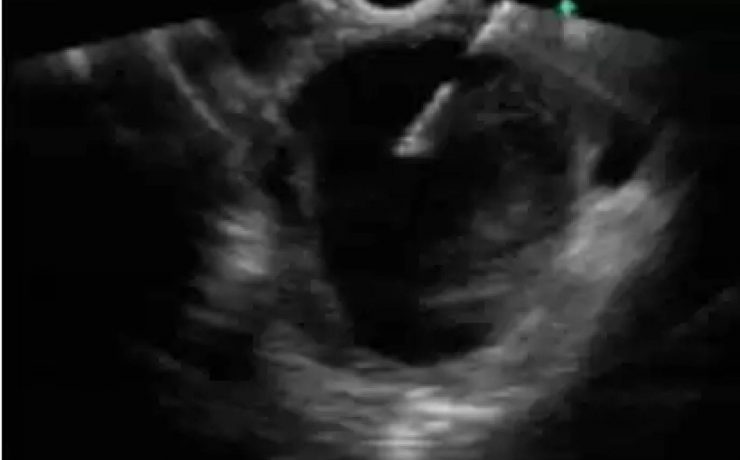

EL MODO A (modo de amplitud) fue el primer método utilizado para formar imágenes de ultrasonido. EL MODO B: modo de brillantez MODO M: modo de movimiento. Tiene su utilidad principal en ecocardiografía tanto en la fetal como en la del adulto. MODO B.- imagen en tiempo real. Al mover